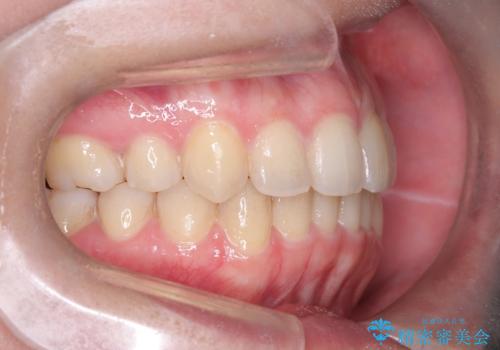

矯正後の後戻り インビザラインで改善

- 前歯のガタツキが気になると来院されました。

マウスピース矯正治療を選択しました。

前歯のガタツキを改善する治療法として、マウスピース矯正が適していることが多いです。

マウスピース矯正は、金属製のブラケットやワイヤーを使用せずに、透明なマウスピースを装着して歯を移動させる方法です。そのため、目立たず、痛みも少ないです。